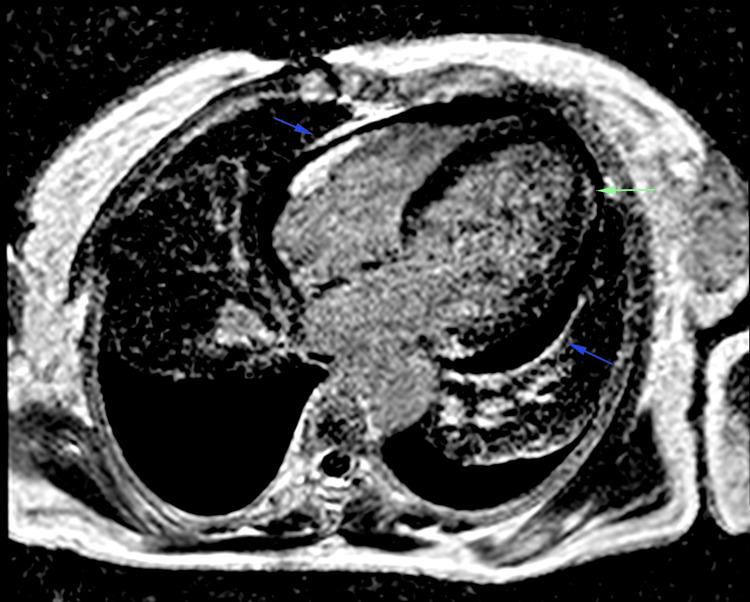

Cryoglobulinemic vasculitis is a rare small-vessel vasculitis leading to multi-organ dysfunction, often associated with chronic infections like hepatitis C virus (HCV), and autoimmune disorders. Most cases involve mixed monoclonal or polyclonal immunoglobulins, presenting symptoms such as purpura, arthralgias, and weakness. Severe organ involvement, particularly cardiac, is rare but potentially life-threatening. We report the case of a 48-year-old woman without prior medical history who presented with acute dyspnea, generalized petechial purpura, and signs of global heart failure. Imaging and laboratory findings indicated cardiomegaly, pericardial effusion, and significant nephrotic syndrome with renal failure. The diagnosis of cryoglobulinaemia was confirmed through histology and serology, showing monoclonal IgM with kappa hypergammaglobulinaemia and complement consumption. Treatment included various immunosuppressants, corticosteroids, and rituximab combined with renal replacement therapy. Following the initiation of treatment and proper management of heart failure, the patient's condition significantly improved. Cardiac involvement in cryoglobulinemic vasculitis, though rare, can lead to severe heart failure. This often involves necrotizing vasculitis of the coronary arteries or systemic inflammation damaging the cardiac muscle, as observed here. Cardiac manifestations with immunosuppressive therapy are reversible despite a poor long-term prognosis for patients with cardiac lesions. In conclusion, cryoglobulinemic vasculitis has a grim prognosis due to its multi-organ impact and the severity of the lesions. Early and aggressive treatment is essential to manage life-threatening acute presentations, even before confirming the diagnosis biologically or histologically.

冷球蛋白血症性血管炎是一种罕见的小血管血管炎,可导致多器官功能障碍,常与丙型肝炎病毒(HCV)等慢性感染以及自身免疫性疾病相关。大多数病例涉及混合性单克隆或多克隆免疫球蛋白,表现为紫癜、关节痛和乏力等症状。严重的器官受累,尤其是心脏受累,虽罕见但可能危及生命。我们报告一例48岁无既往病史的女性,她出现急性呼吸困难、全身性瘀点性紫癜及全心衰体征。影像学和实验室检查结果显示心脏扩大、心包积液以及伴有肾衰竭的显著肾病综合征。通过组织学和血清学检查确诊为冷球蛋白血症,显示单克隆IgM伴κ轻链高球蛋白血症及补体消耗。治疗包括多种免疫抑制剂、糖皮质激素以及利妥昔单抗联合肾脏替代治疗。在开始治疗并对心力衰竭进行恰当管理后,患者病情显著改善。冷球蛋白血症性血管炎中的心脏受累虽罕见,但可导致严重心力衰竭。如此处所见,这通常涉及冠状动脉坏死性血管炎或系统性炎症对心肌的损害。尽管心脏病变患者的长期预后不佳,但免疫抑制治疗后的心脏表现是可逆的。总之,冷球蛋白血症性血管炎因其对多器官的影响及病变的严重性,预后严峻。即使在生物学或组织学确诊之前,早期积极治疗对于处理危及生命的急性表现至关重要。